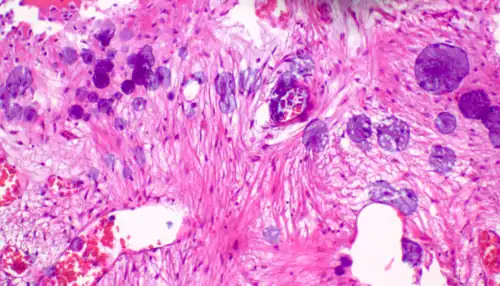

A crush artifact is an artificial elongation and distortion seen in histopathology and cytopathology studies, presumably because of iatrogenic compression of tissues. Distortion can be caused by the slightest compression of tissue and can provide difficulties in diagnosis.[2][3] It may cause chromatin to be squeezed out of nuclei.[4] Inflammatory and tumor cells are most susceptible to crush artifacts.[4]